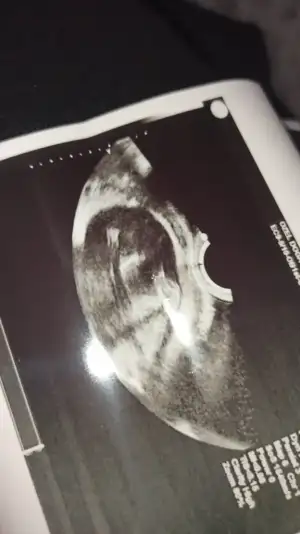

Sanırım artık hareket kısıtlamaları başladı hayırlısı olsun